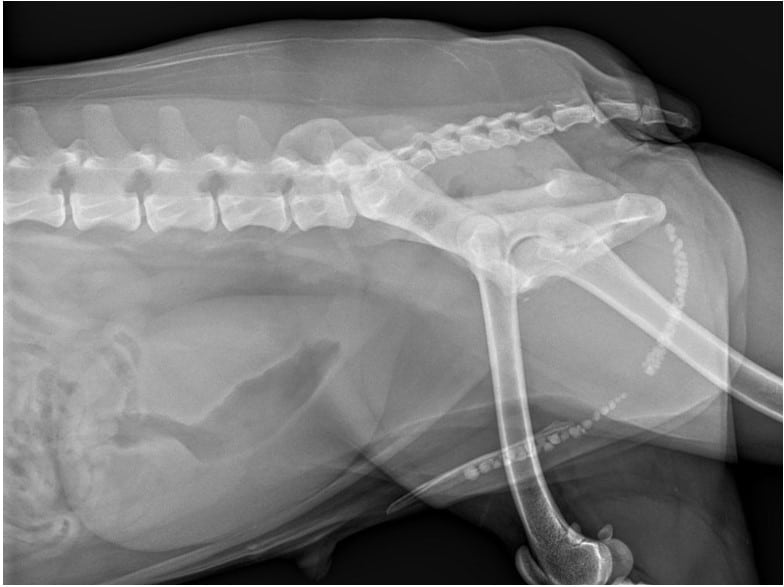

Pre-Surgical Evaluation

Typically, before dog TECA, the vets carry out:

- A complete ear assessment (usually under sedation)

- CT scan or another type of advanced imaging of the middle ear

- Culturing and sensitivity testing

- Anesthesia safety blood work

- Neurologic exam (facial nerve function)

Proper planning leads to fewer problems and better results.